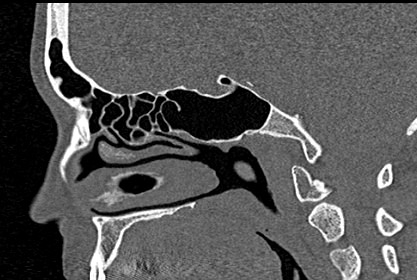

Золотым стандартом в диагностике патологических процессов пазух носа является мультиспиральная компьютерная томография, которая является быстрым безболезненным и неинвазивным (то есть без вмешательства в организм) способом исследования состояния синусов. Метод основан на проникающей способности ионизирующего излучения и получения изображений органов и тканей организма за счет разной степени поглощения ими рентгеновских лучей.

На основе полученных данных цифровые приложения томографов создают трехмерные реконструкции пазух носа, что позволяет оценить пространственное взаимоотношение анатомических структур и помогает в диагностике патологии околоносовых пазух.

Мультиспиральная компьютерная томография дает информацию о состоянии полости носа, носовой перегородки, степени воздушности околоносовых пазух, путей дренирования синусов, состоянии слезных каналов. Сканирование позволяет оценить толщину слизистой, наличие патологического содержимого в просвете пазух (уровня «жидкости»), выявить опухолевые образования. С помощью КТ можно провести точную диагностику травматических повреждений костей лицевого черепа, определить локализацию инородных тел, попавших в полости синусов.

С помощью объемной реконструкции можно перед оперативным вмешательством увидеть особенности анатомии ЛОР-органов, определить точное расположение патологического очага по отношению к окружающим тканям. Компьютерная томография помогает в диагностике аномалий развития придаточных пазух носа, слезоотводящих каналов.